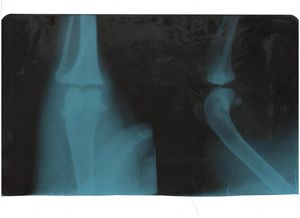

Внедрение рентгенограммы является всераспространенным способом обнаружения задачи артрита. Травмы могут включать переломы, вывих суставов и т.п. Износ и трение суставов делает кошек более восприимчивыми к остеоартриту.Травматический артрит: эта форма артрита является результатом внезапной травмы суставов. Такие случаи, как падение с высоты неловким образом и другие подобные серьезные травмы являются причиной проблемы травматического артрита у кошки.

Рентгенограмма помогает увидеть суставы и, таким макаром, получается более полное представление о каких-либо проблемах. И хотя рентгенограммы помогают в диагностике проблемы артрита, проведение анализов крови также полезно для исключения возможности наличия других проблем со здоровьем.